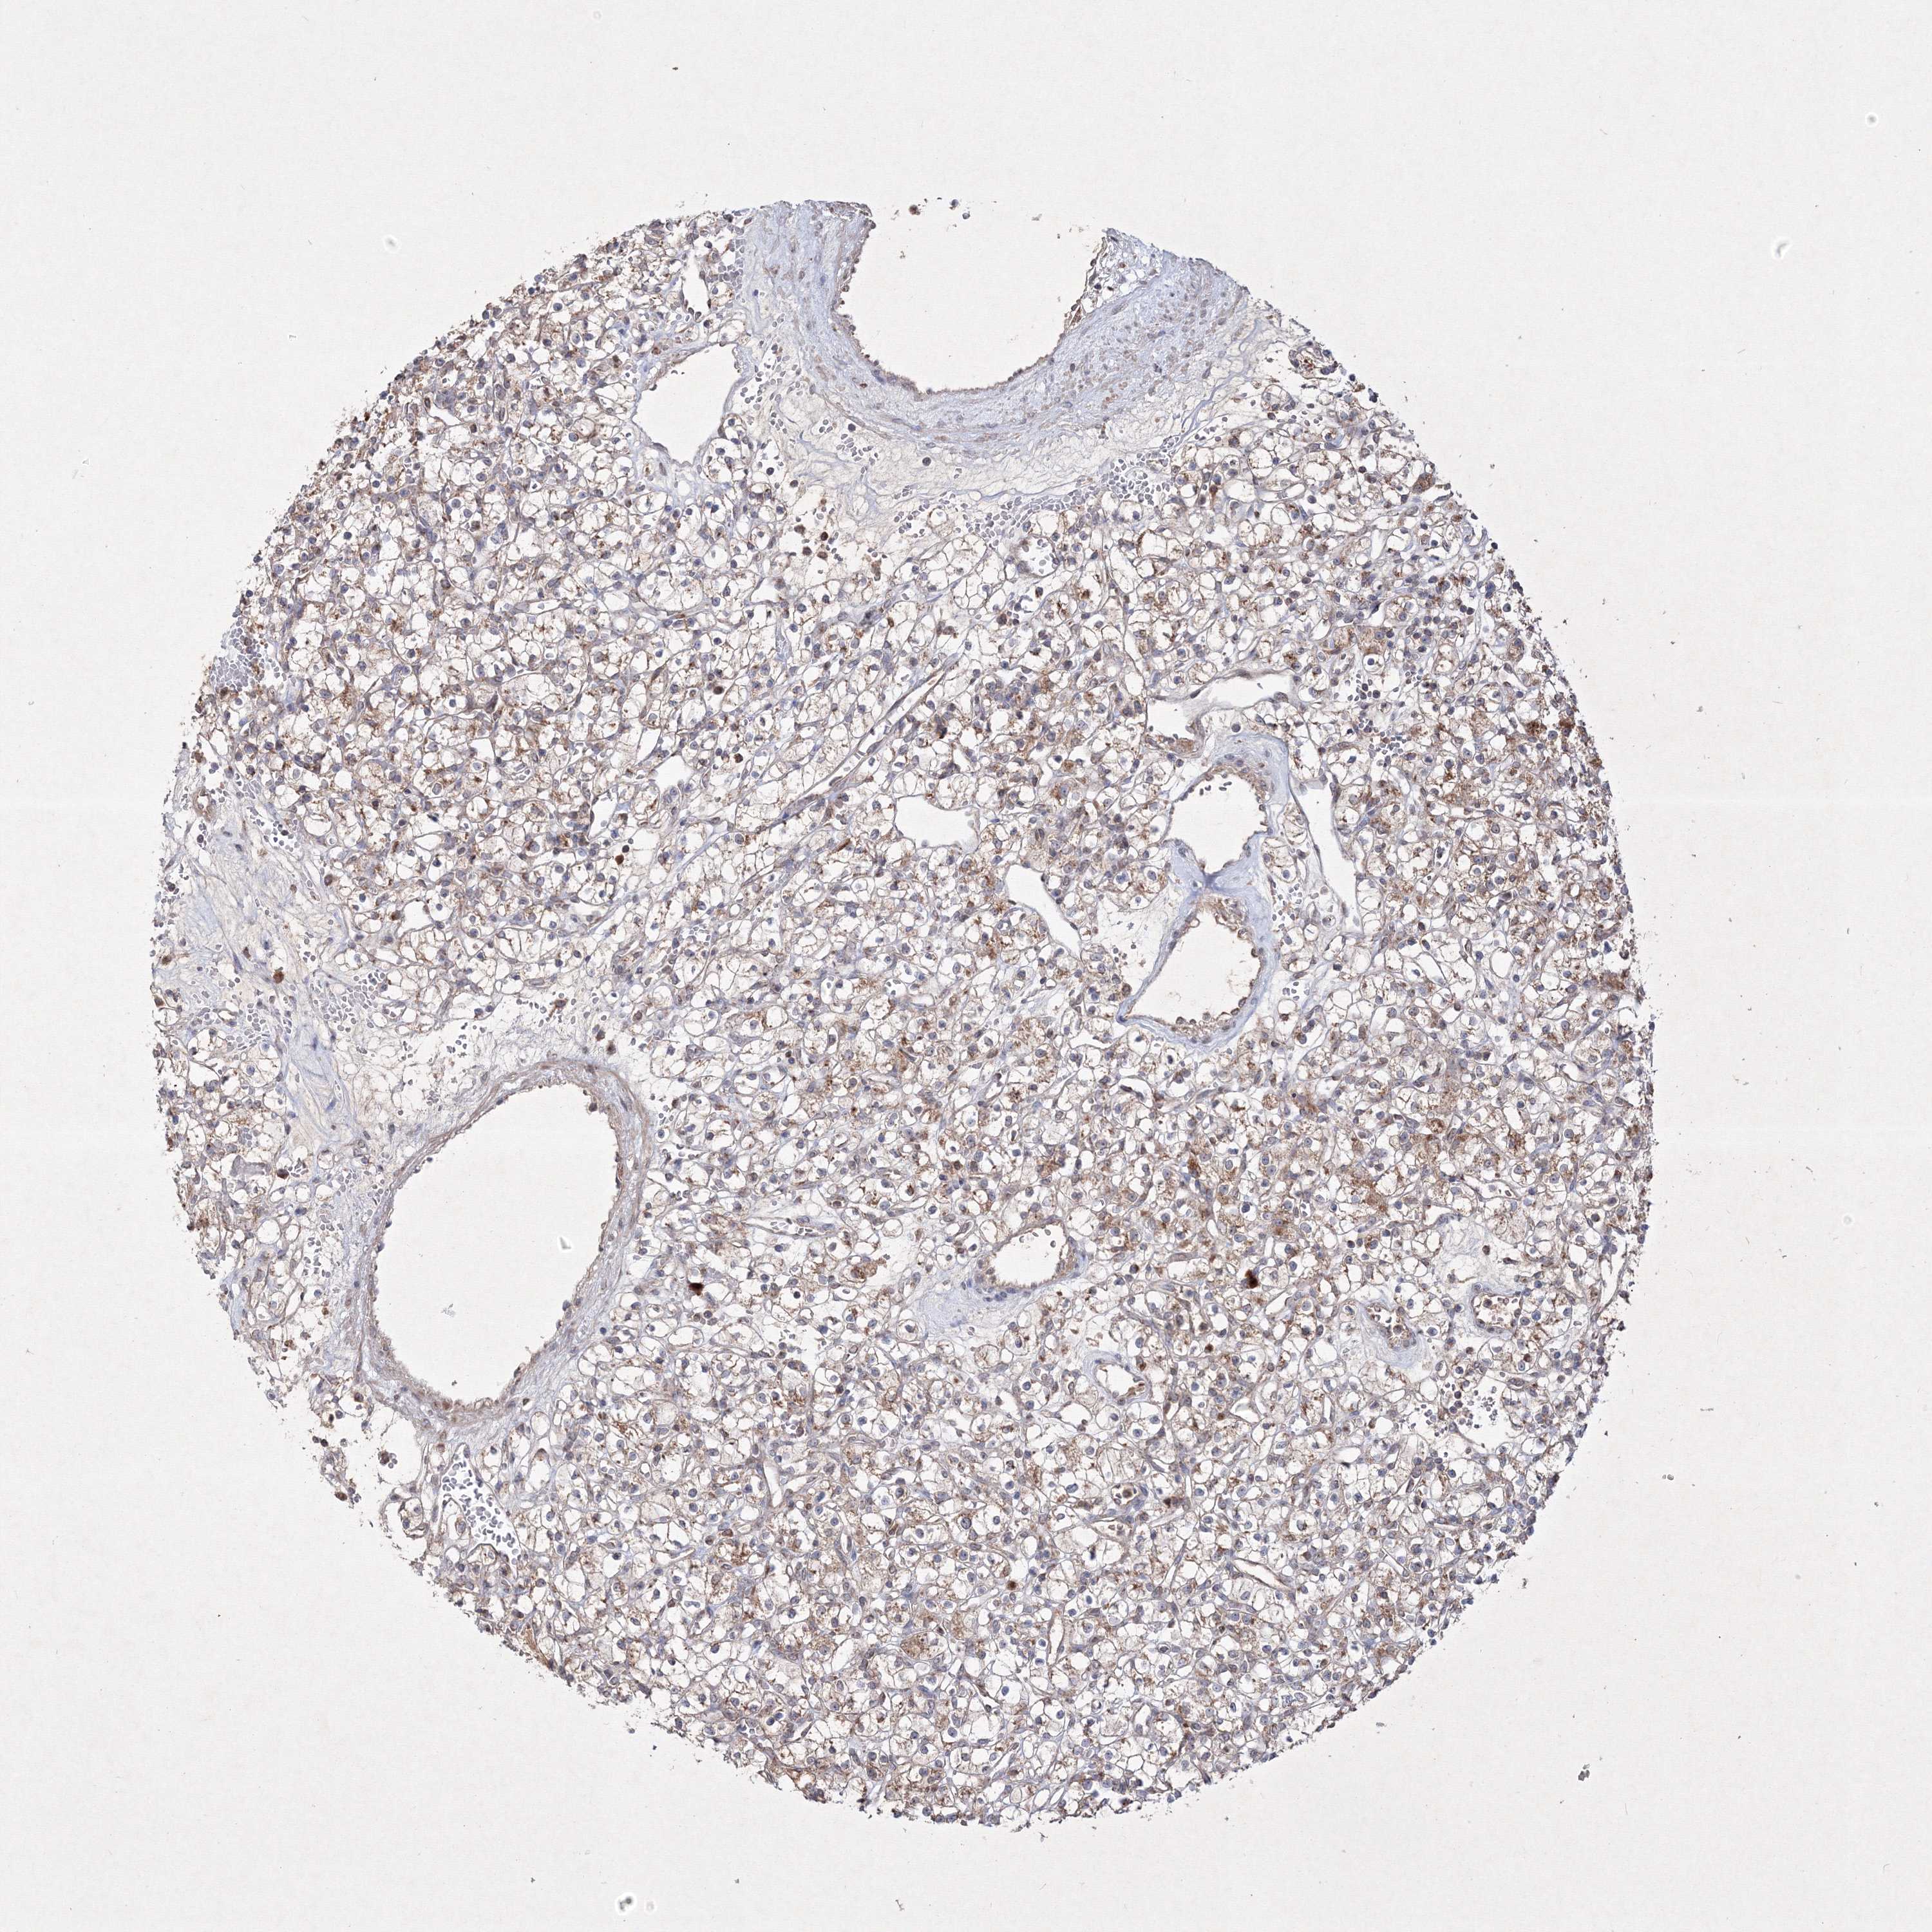

KIDNEY RENAL CLEAR CELL CARCINOMA (VALIDATION) - Interactive survival scatter ploti

The Survival Scatter plot shows the clinical status (i.e. dead or alive) for all individuals in the patient cohort, based on the same data that underlies the corresponding Kaplan-Meier plots. Patients that are alive at last time for follow-up are shown in blue and patients who have died during the study are shown in red.

The x-axis shows the expression levels (FPKM) of the investigated gene in the tumor tissue at the time of diagnosis. The y-axis shows the follow-up time after diagnosis (years). Both axes are complimented with kernel density curves demonstrating the data density over the axes. The top density plot shows the expression levels (FPKM) distribution among dead (red) and alive patients (blue). The right density plot shows the data density of the survived years of dead patients with high and low expression levels respectively, stratified using the cutoff indicated by the vertical dashed line through the Survival Scatter plot. This cutoff is automatically defined based on the FPKM cutoff that minimizes the p-score. The cutoff can be changed by dragging the vertical line or by entering a cutoff value in the square labeled "Current cut-off".

Under the Survival Scatter plot the p-score landscape (black curve; left axis) is shown together with dead median separation (red curve; right axis). Dead median separation is the difference in median mRNA expression between patients who have died with high and low expression, respectively. It is calculated as follows: median FPKM expression of dead patients with high expression - median FPKM expression of dead patients with low expression. This is intended to aid the user in visually exploring custom cutoffs and the associated p-scores and dead median separation.

Individual patient data is displayed and can be filtered by clicking on one or more of the category buttons on the top of the page. Categories describing expression level and patient information include: high, low, alive, dead, female, male and tumor stages. The scale of the x-axis can be toggled between linear and log-scale by clicking on the "x log" button. Mouse-over function shows TCGA ID, patient information and mRNA expression (FPKM) for each patient.

& Survival analysisi

Kaplan-Meier plots summarize results from analysis of correlation between mRNA expression level and patient survival. Patients were divided based on level of expression into one of the two groups "low" (under cut off) or "high" (over cut off). X-axis shows time for survival (years) and y-axis shows the probability of survival, where 1.0 corresponds to 100 percent.

PEX13 is not prognostic in Kidney Renal Clear Cell Carcinoma (validation)

Best expression cut offi

Based on the FPKM value of each gene, patients were classified into two groups and association between prognosis (survival) and gene expression (FPKM) was examined. The best expression cut-off refers the FPKM value that yields maximal difference with regard to survival between the two groups at the lowest log-rank P-value. Best expression cut-off was selected based on survival analysis .

When clicking on this number, the vertical dashed line indicating cut-off, the interactive survival plot, and the Kaplan-Meier curve will be adjusted to show results based on the best expression cut-off.

: 14.73

P scorei

Log-rank P value for Kaplan-Meier plot showing results from analysis of correlation between mRNA expression level and patient survival.

N/A

TCGA RNA samplesi

RNA-seq data is reported as average FPKM (number Fragments Per Kilobase of exon per Million reads), generated by the The Cancer Genome Atlas (TCGA) .

Normal distribution across the dataset is visualized with box plots, shown as median and 25th and 75th percentiles. Points are displayed as outliers if they are above or below 1.5 times the interquartile range. FPKM values of the individual samples are presented next to the box plot.

Average pTPM 15.0

Number of samples 100